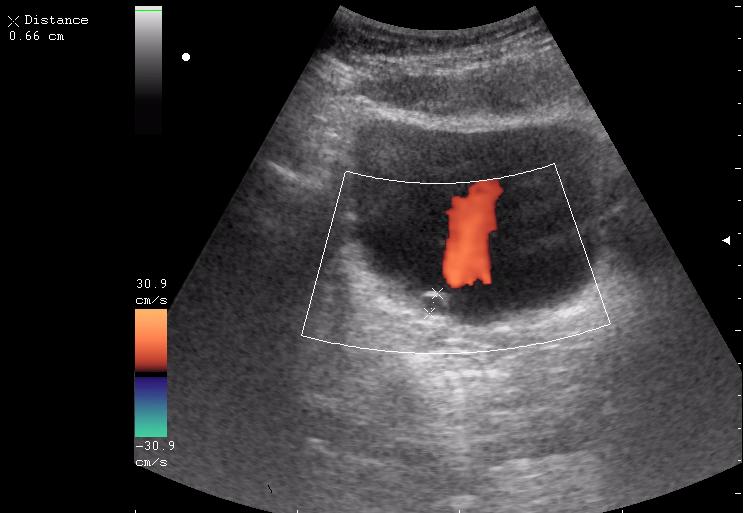

Продольное сканирование мочевого пузыря После легкой перкуссии мочевого пузыря

зато какое наполнение! а осадок убедительный! а же не 7-кой смотрела!На сонограммах неубедительно продемонстрирован осадок да и стенки м.п. не утолщены.